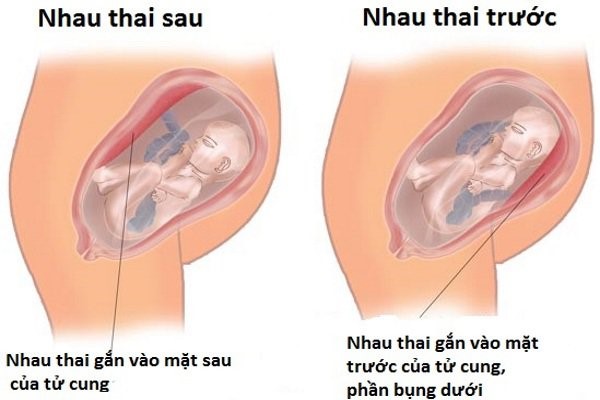

Hiện tượng nhau bám mặt trước là gì?

Vậy nhau bám mặt trước là gì? Nhau thai sau khi thụ tinh sẽ được hình thành ở phần trên của tử cung. Tuy nhiên khác với những trường hợp như nhau bám trên thành tử cung, nhau bám trên thành tử cung thì nhau bám mặt trước tức là nhau sẽ ở phần dưới tử cung. Điều này có nghĩa là thai sẽ nằm ở ngay phía trước đầu em bé với phần sau là bào thai.